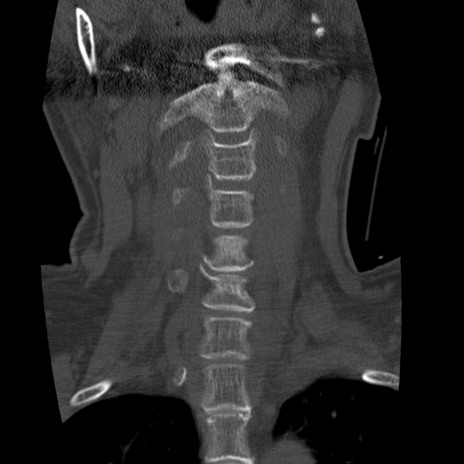

症例50 頚椎CT(冠状断像)

頚椎CT